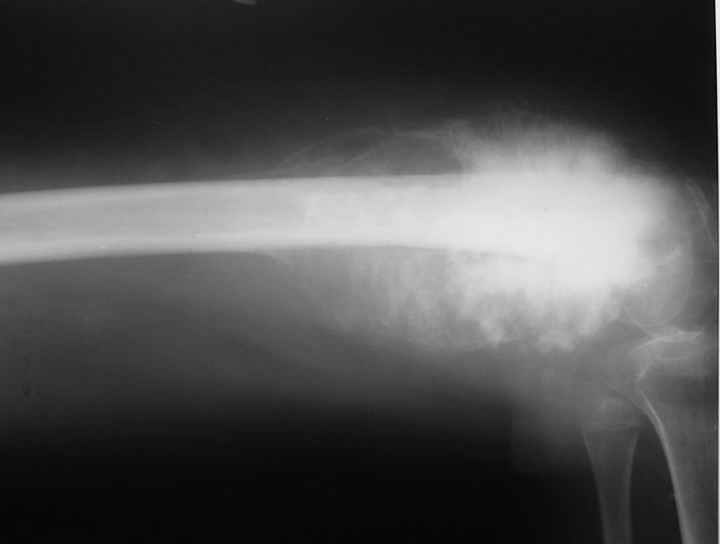

Запущенная опухоль

Девочка 14 лет. Остеогенная саркома бедренной кости. Множественные метастазы в лёгких. Долго лечили от разных форм артрита в одном из городов Татарстана. Ленар Рашитов